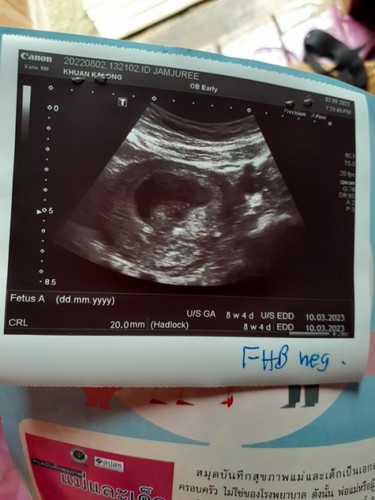

ซาว10wพบถุงตั้งครรภ์ หมอบอกว่า ไม่พบตัวเด็กหัวใจเด็กไม่มีเด็กหยุดการเจริญเติบ

กังวลใจมากๆค่ะ หมอส่งไปซาวใหม่อีกรอบ ร.พ.เมือง อาทิตย์หน้า ต้องลุ้นว่าลูกจะอยู่กับเราไหมคุณแม่บ้านไหนพบแบบนี้บ้างคะ

ทำใจรอเลยค่ะแม่ จากการซาวได้8wต้องได้ยินแล้วค่ะ เราก็เป็นแบบนี้ตอน13wหมอให้ขูดมดลูกเลย